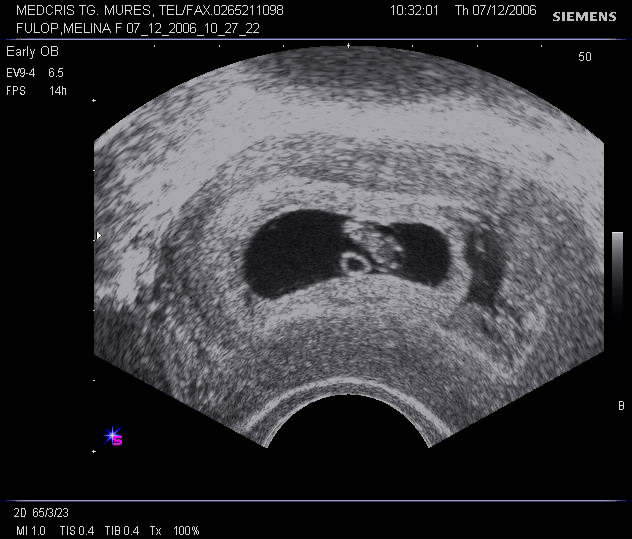

SARCINA DE TRIMESTRUL I - ASPECTE PATOLOGICE

Sarcina de trimestrul I - aspecte patologice Ecografia transvaginala este indispensabila investigatiei sarcinii anormale, in special in trim. I Criterii pentru diagnosticul sonografic de sarcina intrauterina incipienta, anCiteste tot ... 2393 cuvinte

Dimensiune medie + cu poze |